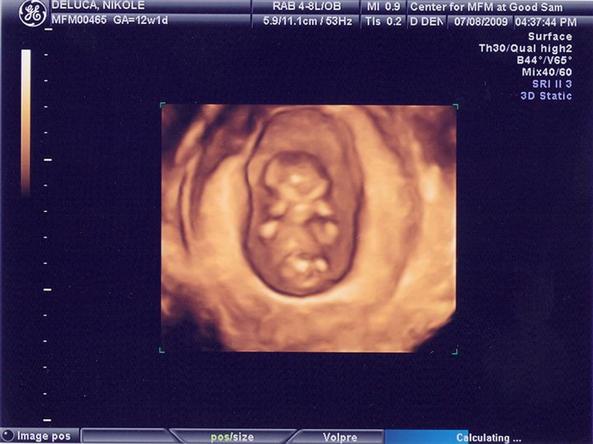

I sit here thinking of what life was like one year nine months ago... not sleep deprived, not a stretch mark to be found, twenty+ pounds lighter and out drinking with my friends until the wee small hours of the morning. But in an instant (May 13th at 5:15am to be exact)... my life changed. Stopping dead in its tracks. After 18 months of trying for a baby, a miscarriage, surgery to make "repairs", an ectopic pregnancy, and holistic health counseling... I. Am. Pregnant. WHAT THE!? HOW THE!? WHEN THE?! Oh my God! 16 weeks (exactly) of nausea, dry heaving... how the hell did the the human race continue if this is what you feel like - without an end in sight??? 25 weeks and 5 days wondering what he'll look like... will he have my skin tone (oh please God... be kind to him), will he have his father's hands (oh PLEASE God... no), will be have my legs (for his sake... please God). So much to guess, so much to dream about. And, then the day came, January 29th at 12:30pm... "Take your wife out for a nice dinner... this will be the last one you two have as a childless couple. I'll see you guys at 10pm at the hospital." Those words changed everything. Twelve hours later... holy ****. Is this for real?? You have GOT to be kidding me! I ask again God, how the HELL did the human race continue?? I revere the wo/man who invented the Epidural... I love you. You are my hero(ine)... Two hours, 24 minutes later, for the first time, in months, I felt... empty. Where there was a fullness, now... nothing. MY job was done... The job was now OURS. Our son was born. OUR lives have now changed FOREVER. Logan Joseph Creed De Luca entered the world at 2:54pm on Saturday, January 30th... a healthy 8 pounds 6 ounces and 21 3/4 inches. To say that the last year has had its FAIR share of ups-and-downs would be understatement - but that's what we signed up for. I now sit here on the eve of Logan Joseph Creed's FIRST birthday... thanking God for all that he has given to me. Thanking God that he kept him in our life. I sit here watching my son play with his father. Trying to imitate his father... Babbling up a storm while wreaking havoc on our living room... running in circles, pointing at the lamp: "Pret-ty". Calling out for "Tayl-yah"... "Wheh flow-wah?" Trying to find the faults in the corral system keeping him in the living room - like those dinosaurs in Jurassic Park... Joe and I just look at each other and think: "This kid is gonna keep us on our toes... wouldn't have it any other way." Image Attachment(s):